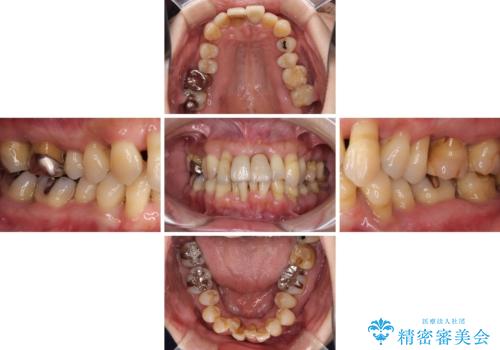

- 近医に通い続けるも、一向に不快感が改善しないとのことで来院された患者様です。

診察を行ったところ、重度歯周病の状態の上に上下の歯列が著しい叢生という状態でした。

歯周初期治療として抜歯や歯槽骨再生治療を行い、さらに歯周ポケット除去を行った後に矯正治療で歯列を整えて行くこととしました。